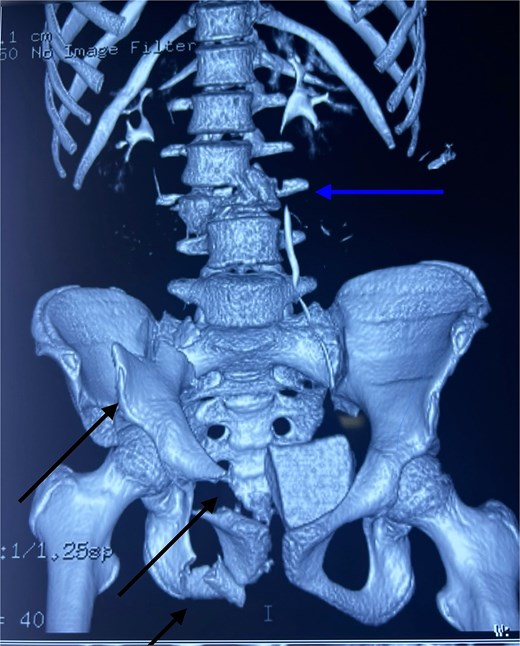

After hemodynamic stabilization, an emergency full-body computed tomography (CT) scan was performed, revealing a minimal pneumothorax, a significant pneumopericardium (Fig. 1), multiple pelvic fractures, and a vertebral fracture at the L3 level (Fig. 2). Blood tests showed a hemoglobin level of 8 g/dL, prompting transfusion of two units of packed red blood cells. Following the onset of chest pain, a percutaneous decompression of the pneumopericardium was performed, resulting in rapid clinical improvement. The patient was then admitted to the intensive care unit for close monitoring. She subsequently underwent surgical osteosynthesis from L2 to L4.

3D CT reconstruction showing L3 vertebral fracture (upper arrow) and multiple pelvic fractures (lower arrows).